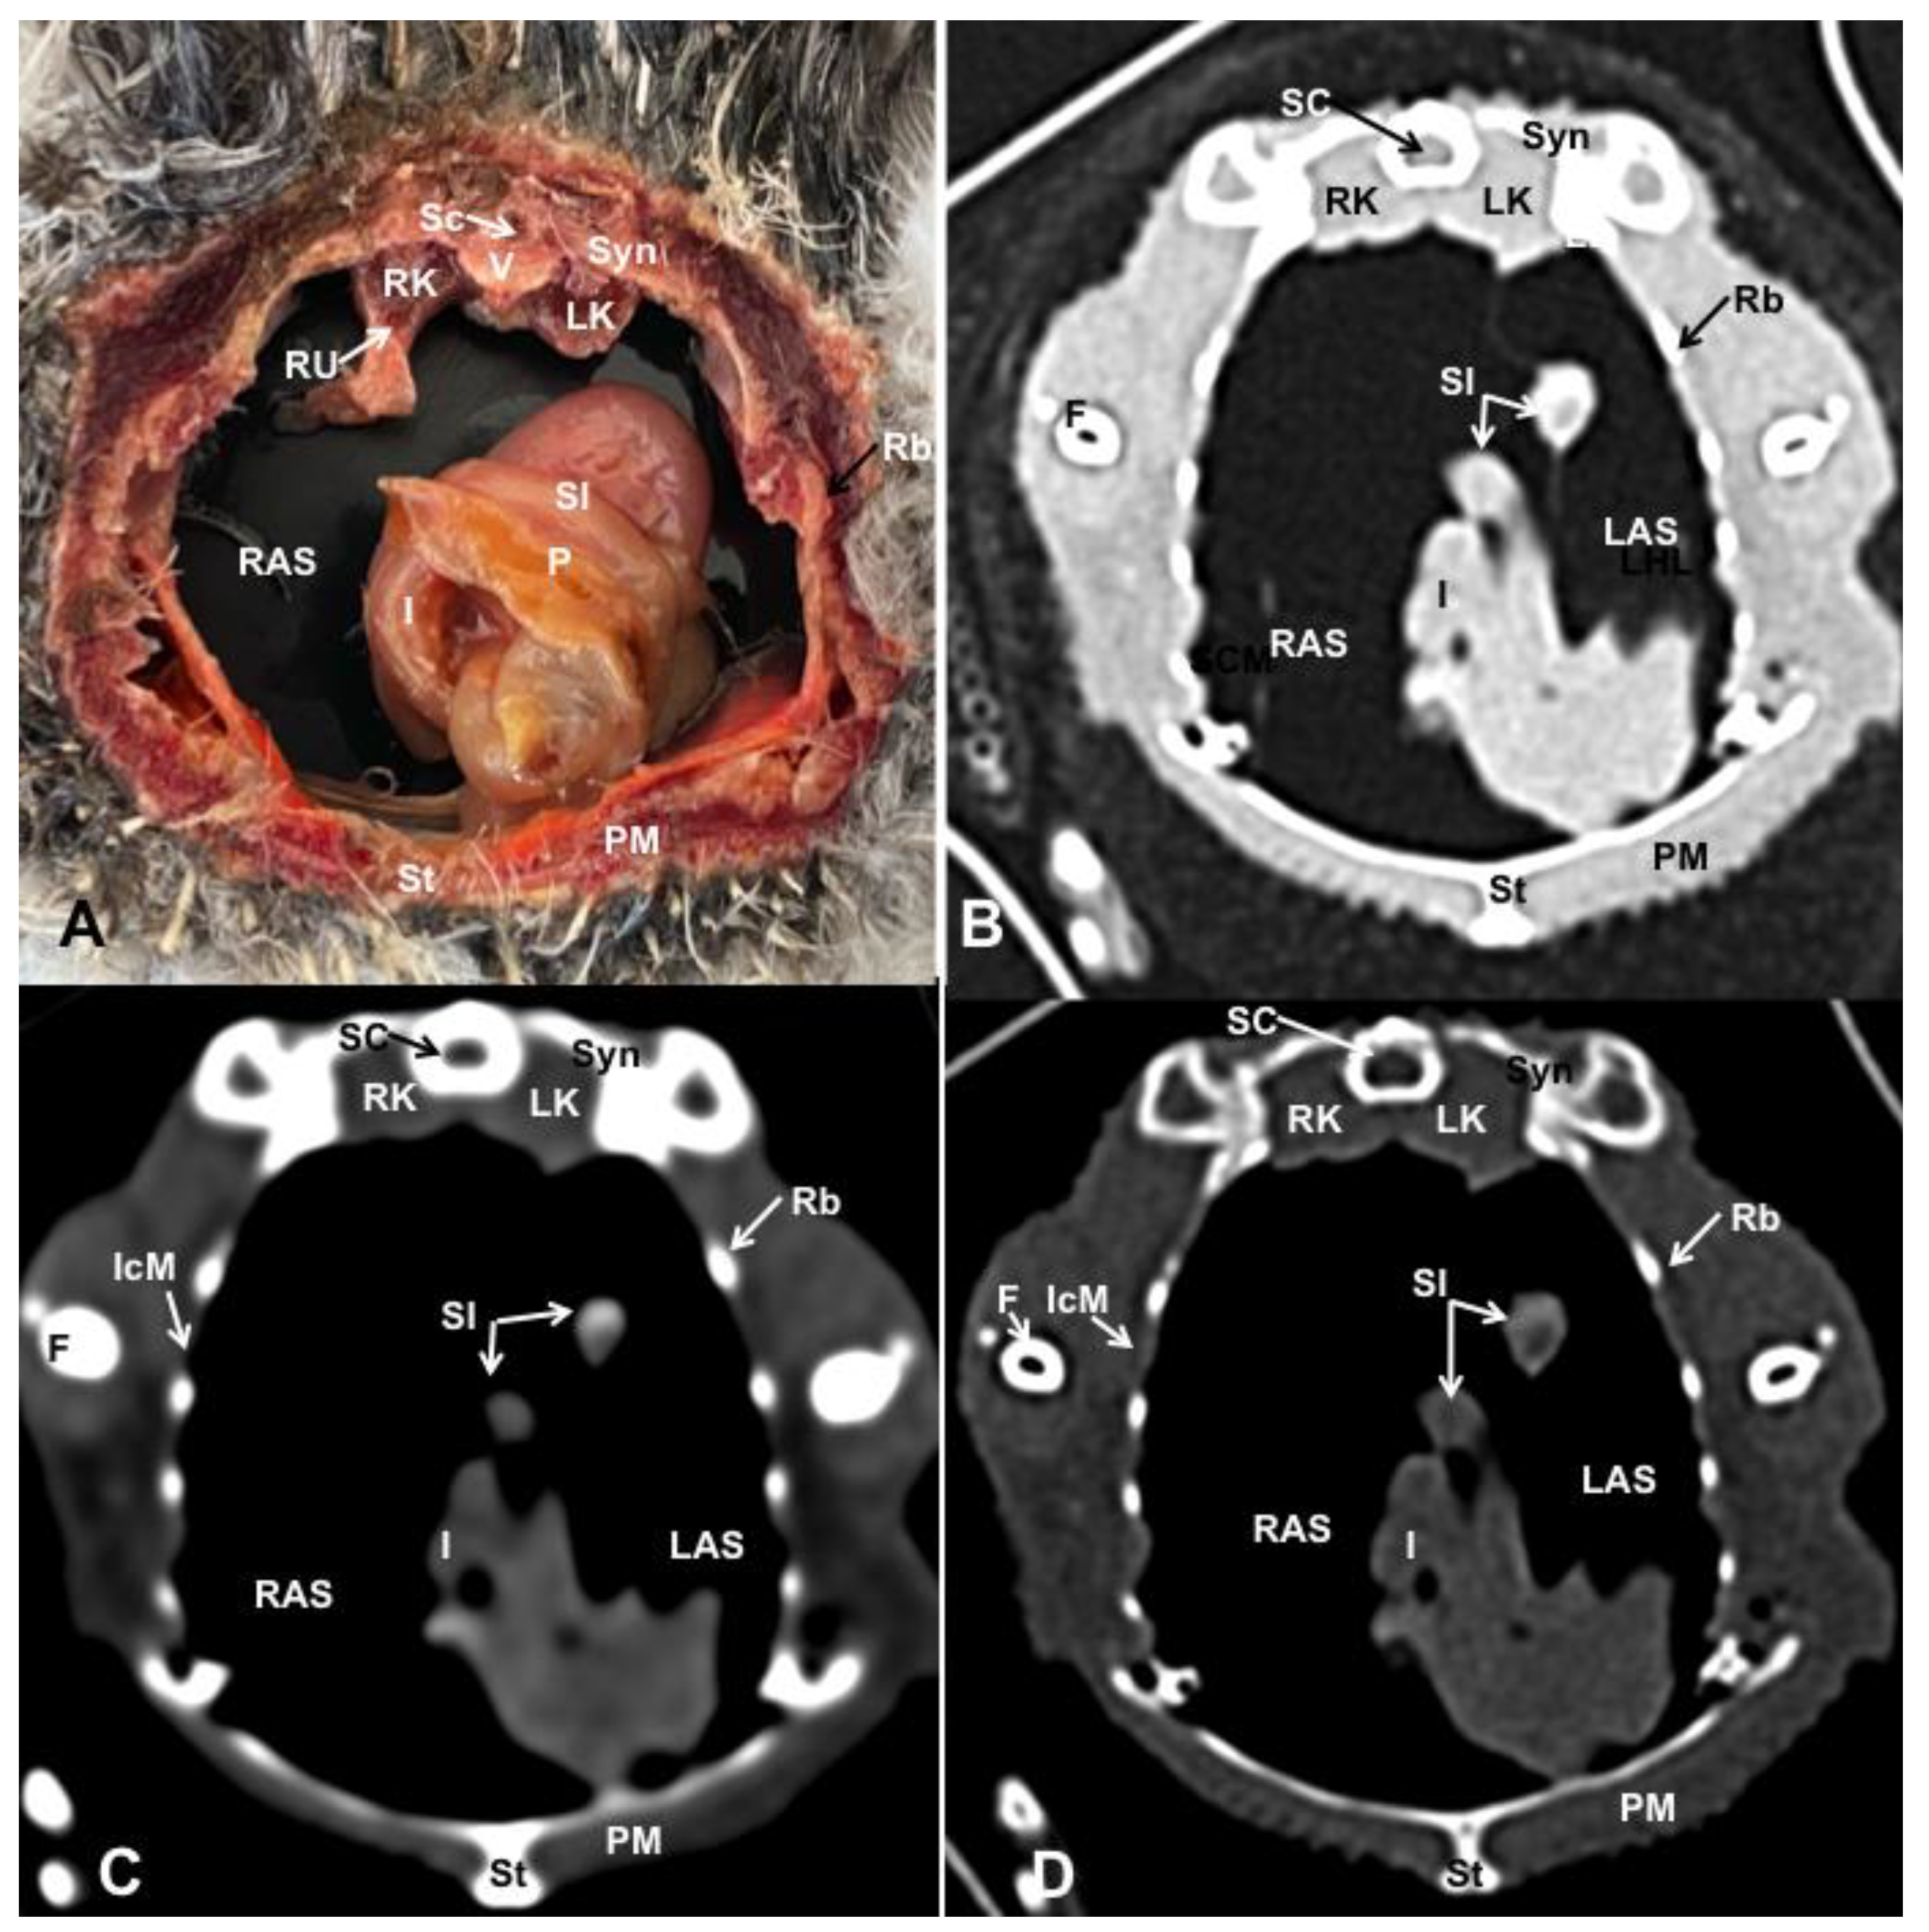

3. Results

3.1. Anatomical Dissections and Cross-Sections

3.2. Computed Tomography Images